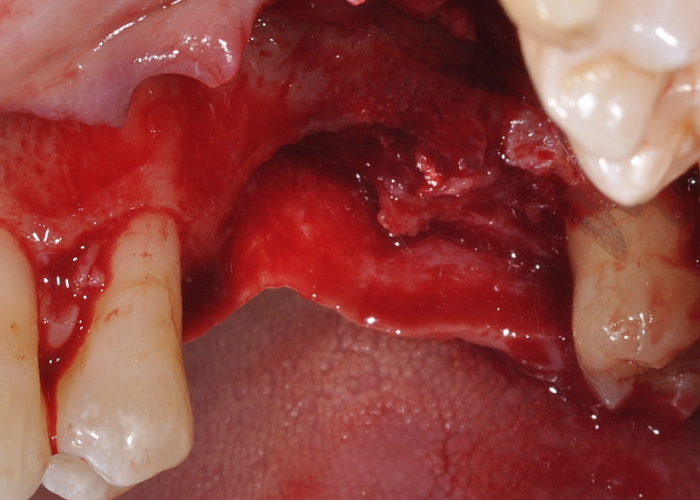

Хирургическое устранение рецессий десны. Восстановление межзубного сосочка. Показания. Методики. Разбор ошибок и осложнений.